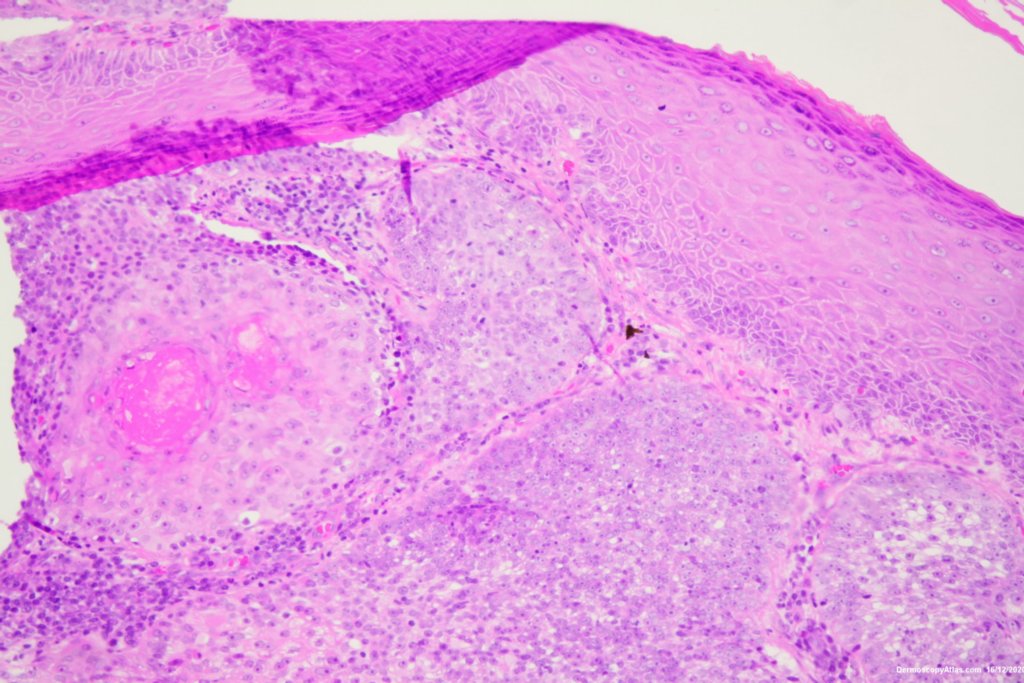

Image Number #3578 (Lentigo Maligna)

Diagnosis: Lentigo Maligna

Description: Pigmented lesion cheek and pink nodule

Elderly male with no past history of melanoma developed these two lesions over a year or so. The lentigo maligna was easy to diagnose on the clinical and dermatoscopy but the nodule was more difficult. Was it an amelanotic melanoma, BCC or SCC were the initial thoughts. Histology showed a well differentiated sebaceous carcinoma. The two lesions were excised in the same specimen with 5 mm margins. Studies failed to show the mutation for the Muir Torre syndrome which can be seen with sebaceous carcinoma.